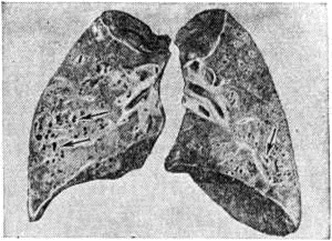

Рис. 2.

Макропрепарат лёгких (фронтальный разрез) при Муковисцидозе: стрелками указаны множественные абсцессы, окружённые разрастаниями соединительной ткани.

Застой вязкой мокроты в бронхах приводит к обтурационным ателектазам, компенсаторной эмфиземе и вторичному инфицированию. Развивается хронический бронхит (смотри полный свод знаний), гнойные бронхоэктазы, хронический пневмония с абсцедированием (рисунок 2).